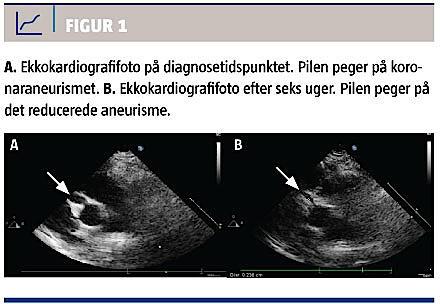

Patienten blev behandlet med i.v. givet immunglobulin (IVIG) og aspirin. En ekkokardiografi viste et 4,3 mm stort fussiformt aneurisme på højre koronararterie (Figur 1A). Seks uger efter behandlingsstart var aneurismet reduceret til 2,6 mm (Figur 1B). Efter fem måneder var det yderligere reduceret til 1,9 mm, og aspirinbehandlingen blev seponeret. Efter et år var der ingen koronaraneurismer ved ekkokardiografi.